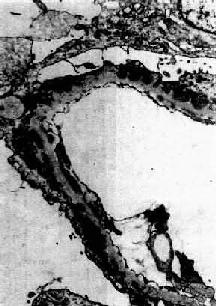

图12-9 毛细血管内增生性肾小球肾炎

电镜下见驼峰状沉积物位于毛细血管基底膜表面。沉积物表面有上皮细胞覆盖,上皮细胞足突消失